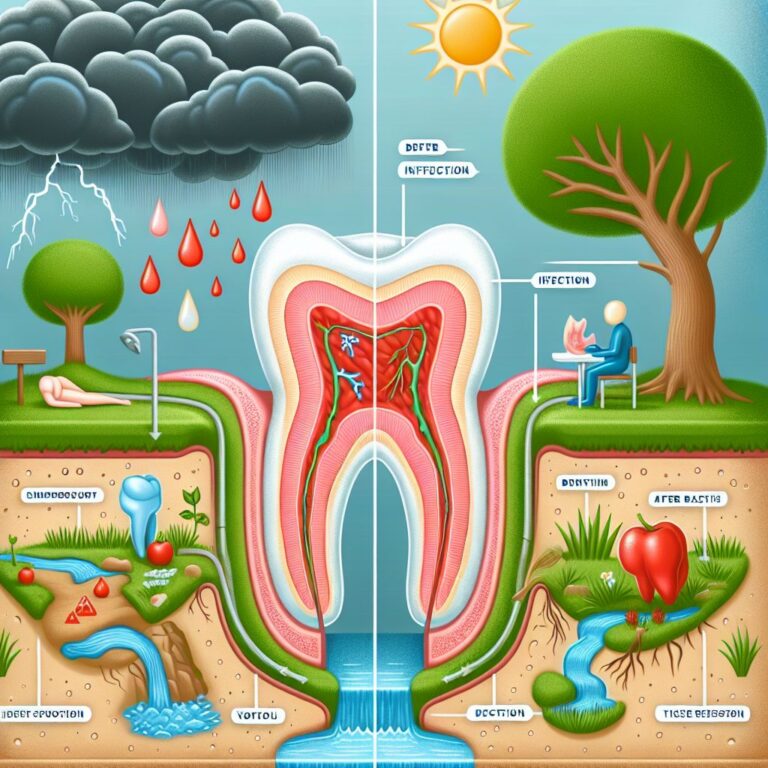

Gum recession can leave tooth roots exposed, leading to sensitivity, increased decay risk, and an aged appearance. Fortunately, modern dentistry offers effective solutions through gum grafting procedures. One of the most common questions patients ask is about where these graft tissues come from – and for good reason.

The extent of recession directly influences material selection. Small, localized areas may be ideally treated with autogenous tissue for optimal esthetics and function. Larger areas or multiple sites might benefit from donor materials that eliminate harvest site limitations. Your periodontist will assess the dimensions of recession and the amount of tissue needed to achieve the desired outcome.

The thickness of tissue required also factors into the decision. Some cases require the substantial thickness that only palatal tissue can reliably provide, while others may achieve excellent results with thinner donor materials.

Medical conditions significantly influence graft selection. Patients with bleeding disorders, compromised immune systems, or those taking medications that affect healing may benefit from approaches that minimize surgical trauma. Donor materials that eliminate the need for palatal harvesting can reduce risks for these patients. Additionally, smoking status, diabetes control, and overall health all factor into the decision-making process.